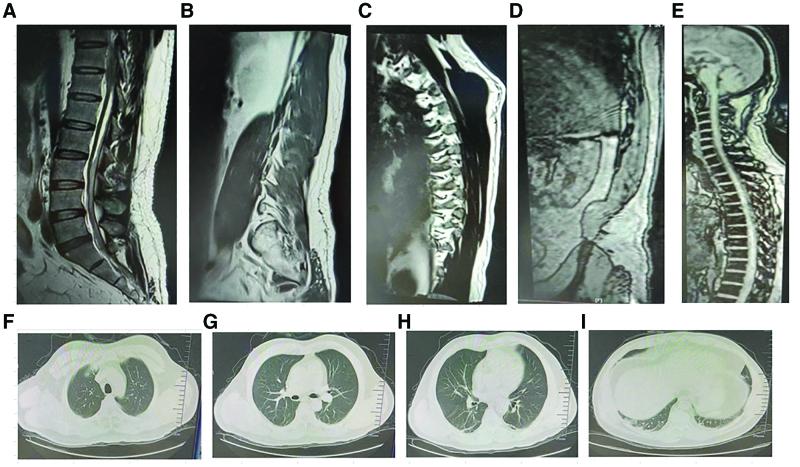

The patient diagnosis was established using thoracic and lumbar magnetic resonance imaging (MRI). Contrast-enhanced thoracic and lumbar MRI revealed subdural (dorsal predominant) short T1 and slightly long T2 bands in the T12-S2 infundibular canal in the scan field, and the subdural hematoma was yet to be distinguished from other diseases. Spinal cord edema was observed in the left vertebral plate and facet joint of the T11 vertebral body, indicative of inflammation. The cerebrospinal fluid (CSF) was positive for COVID-19 nucleic acid.

The patient symptoms significantly improved after 4 weeks of anti-infection and immunomodulatory therapy. Repeat thoracolumbar MRI revealed absorption of the spinal cord hematoma, and the patient was discharged from the hospital. To date, COVID-19-related hematomyelia has not been reported and anti-infective and immunomodulatory therapies may be effective.